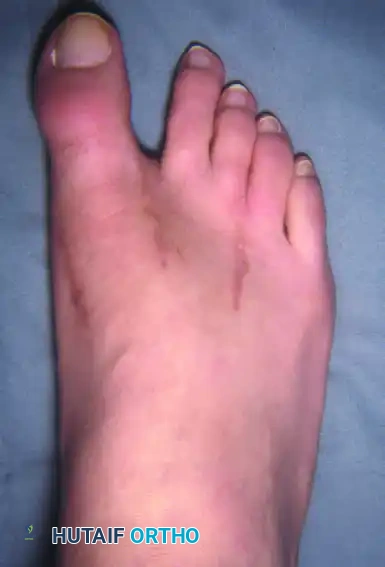

Figure 81-77: (A) Fixed hallux varus after a McBride bunionectomy. (B) Hallux varus after a McBride bunionectomy with fibular sesamoid excision. Removing the fibular sesamoid eliminates the valgus-producing moments of the adductor hallucis and the lateral head of the flexor hallucis brevis.

Figure 81-76: (A) Relatively mild hallux varus with symptomatic degenerative arthritis of the first metatarsophalangeal joint. (B and C) Arthrodesis was chosen as the definitive treatment due to the presence of advanced degenerative joint disease.